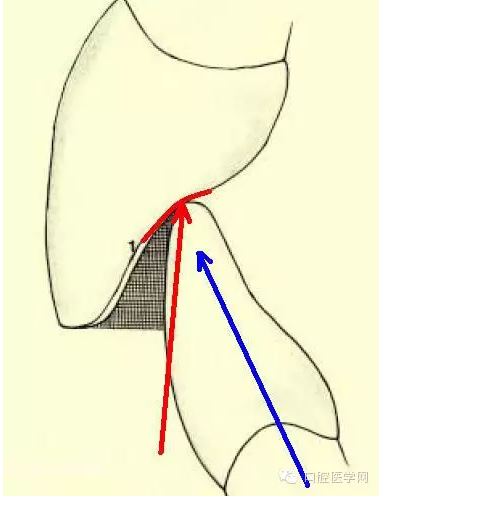

當然,有些人對前牙的受力會有疑問,因為多數(shù)人認為前牙是側(cè)向力,比如前牙做的引導。其實咬合中有一個概念叫Centric Stops(正中止),這一方面是指每個牙齒都有應該它咬合的正確接觸點,另一方面是說,人在CO(尖窩交錯)位時,下頜不能有滑動,以作為肌肉和關節(jié)的保護。而前牙同樣有這樣一個位置。前牙正確的接觸是在前牙舌隆突上,有一個類似臺階的形態(tài),當與下前牙的切緣接觸時會形成向一個延牙齒長軸方向的受力,同時這又限制了下頜的運動范圍(紅線)。如果舌側(cè)沒有這樣一個合適的咬合位置,限制下頜,下頜會形成一個向前的力(藍線)。